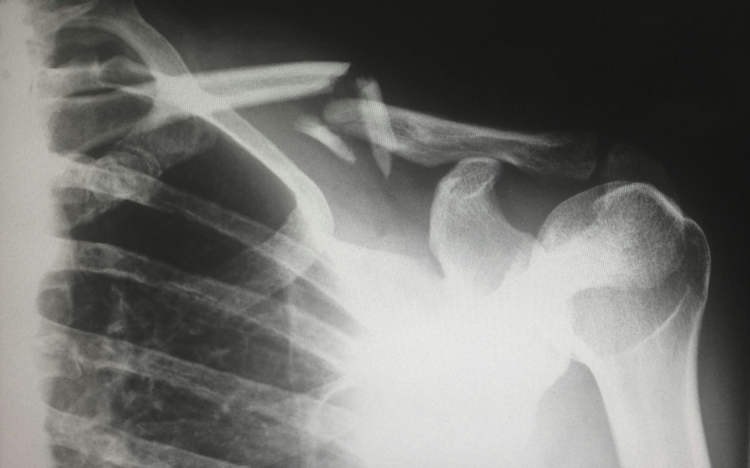

Một người phụ nữ 48 tuổi tại Thành Đô, Trung Quốc đã gây xôn xao dư luận sau khi được chẩn đoán bị gãy xương chỉ vì... xoay người trên giường. Các bác sĩ xác định nguyên nhân là do thiếu hụt vitamin D nghiêm trọng, xuất phát từ thói quen tránh nắng và sử dụng kem chống nắng quá mức suốt nhiều năm.

Theo thông tin từ Bệnh viện Y học Cổ truyền Tân Đô (XinDu), nữ bệnh nhân này chưa từng mặc áo ngắn tay hay để da tiếp xúc với ánh nắng trong suốt thời gian dài. Mỗi khi ra ngoài, bà đều bôi kem chống nắng và che kín cơ thể để tránh nắng. Kết quả kiểm tra cho thấy mức vitamin D trong máu của bà ở mức cực thấp, dẫn đến tình trạng mất xương nhanh và loãng xương nặng.

Trường hợp hy hữu này được bác sĩ Long Song chia sẻ nhằm cảnh báo cộng đồng về nguy cơ từ việc lạm dụng kem chống nắng và tránh nắng cực đoan. Bác sĩ Jiang Xiaobing, Trưởng khoa Phẫu thuật Cột sống Bệnh viện Đại học Y Quảng Châu, cho biết: "Chúng tôi thường gặp những người mặc kín mít từ đầu đến chân để tránh nắng, nhưng điều này thật sự không tốt cho sức khỏe. Toàn bộ xương trong cơ thể được tái tạo hoàn toàn sau mỗi 10 năm, nhưng từ tuổi 30, chúng ta bắt đầu mất dần khối lượng xương với tốc độ 0,5% đến 1% mỗi năm. Việc thiếu vitamin D, không tiếp xúc ánh nắng và chế độ ăn thiếu canxi sẽ cản trở quá trình hấp thụ canxi và làm tăng nguy cơ loãng xương."

Theo các chuyên gia, ánh nắng mặt trời đóng vai trò quan trọng trong việc giúp cơ thể tổng hợp vitamin D, yếu tố then chốt để duy trì sức khỏe xương khớp. Việc tránh nắng hoàn toàn trong thời gian dài không chỉ làm suy yếu miễn dịch mà còn ảnh hưởng nghiêm trọng đến sức khỏe xương.

Dù kem chống nắng được khuyến nghị để bảo vệ làn da, đặc biệt là giảm nguy cơ ung thư da, tuy nhiên, việc lạm dụng quá mức lại tiềm ẩn nhiều rủi ro. Bác sĩ Long Song nhấn mạnh: "Trường hợp của bệnh nhân này là lời cảnh tỉnh cho nhiều người, nhất là những ai bị ám ảnh bởi làn da trắng và mong muốn tránh nắng mọi lúc mọi nơi."

Theo số liệu từ Tổ chức Y tế Thế giới (WHO), khoảng 1 tỷ người trên thế giới hiện đang bị thiếu hụt vitamin D, và xu hướng này có xu hướng gia tăng ở các quốc gia châu Á. Các chuyên gia y tế khuyến cáo nên cân bằng giữa việc bảo vệ da và tiếp xúc ánh nắng hợp lý, đồng thời duy trì chế độ ăn giàu canxi, vitamin D và tập luyện thể dục thể thao thường xuyên để phòng ngừa loãng xương.